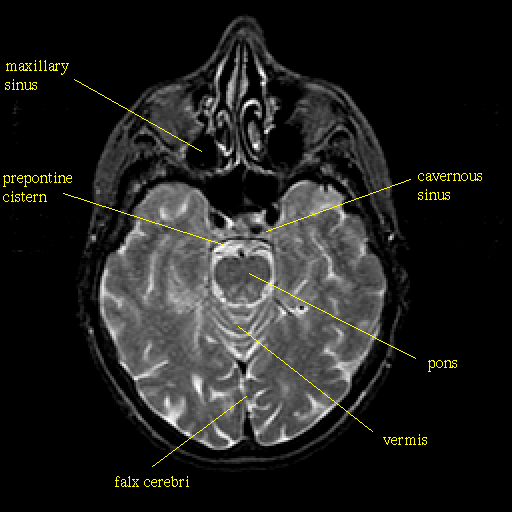

T2-weighted structural MR: Slice 19

Slice 19